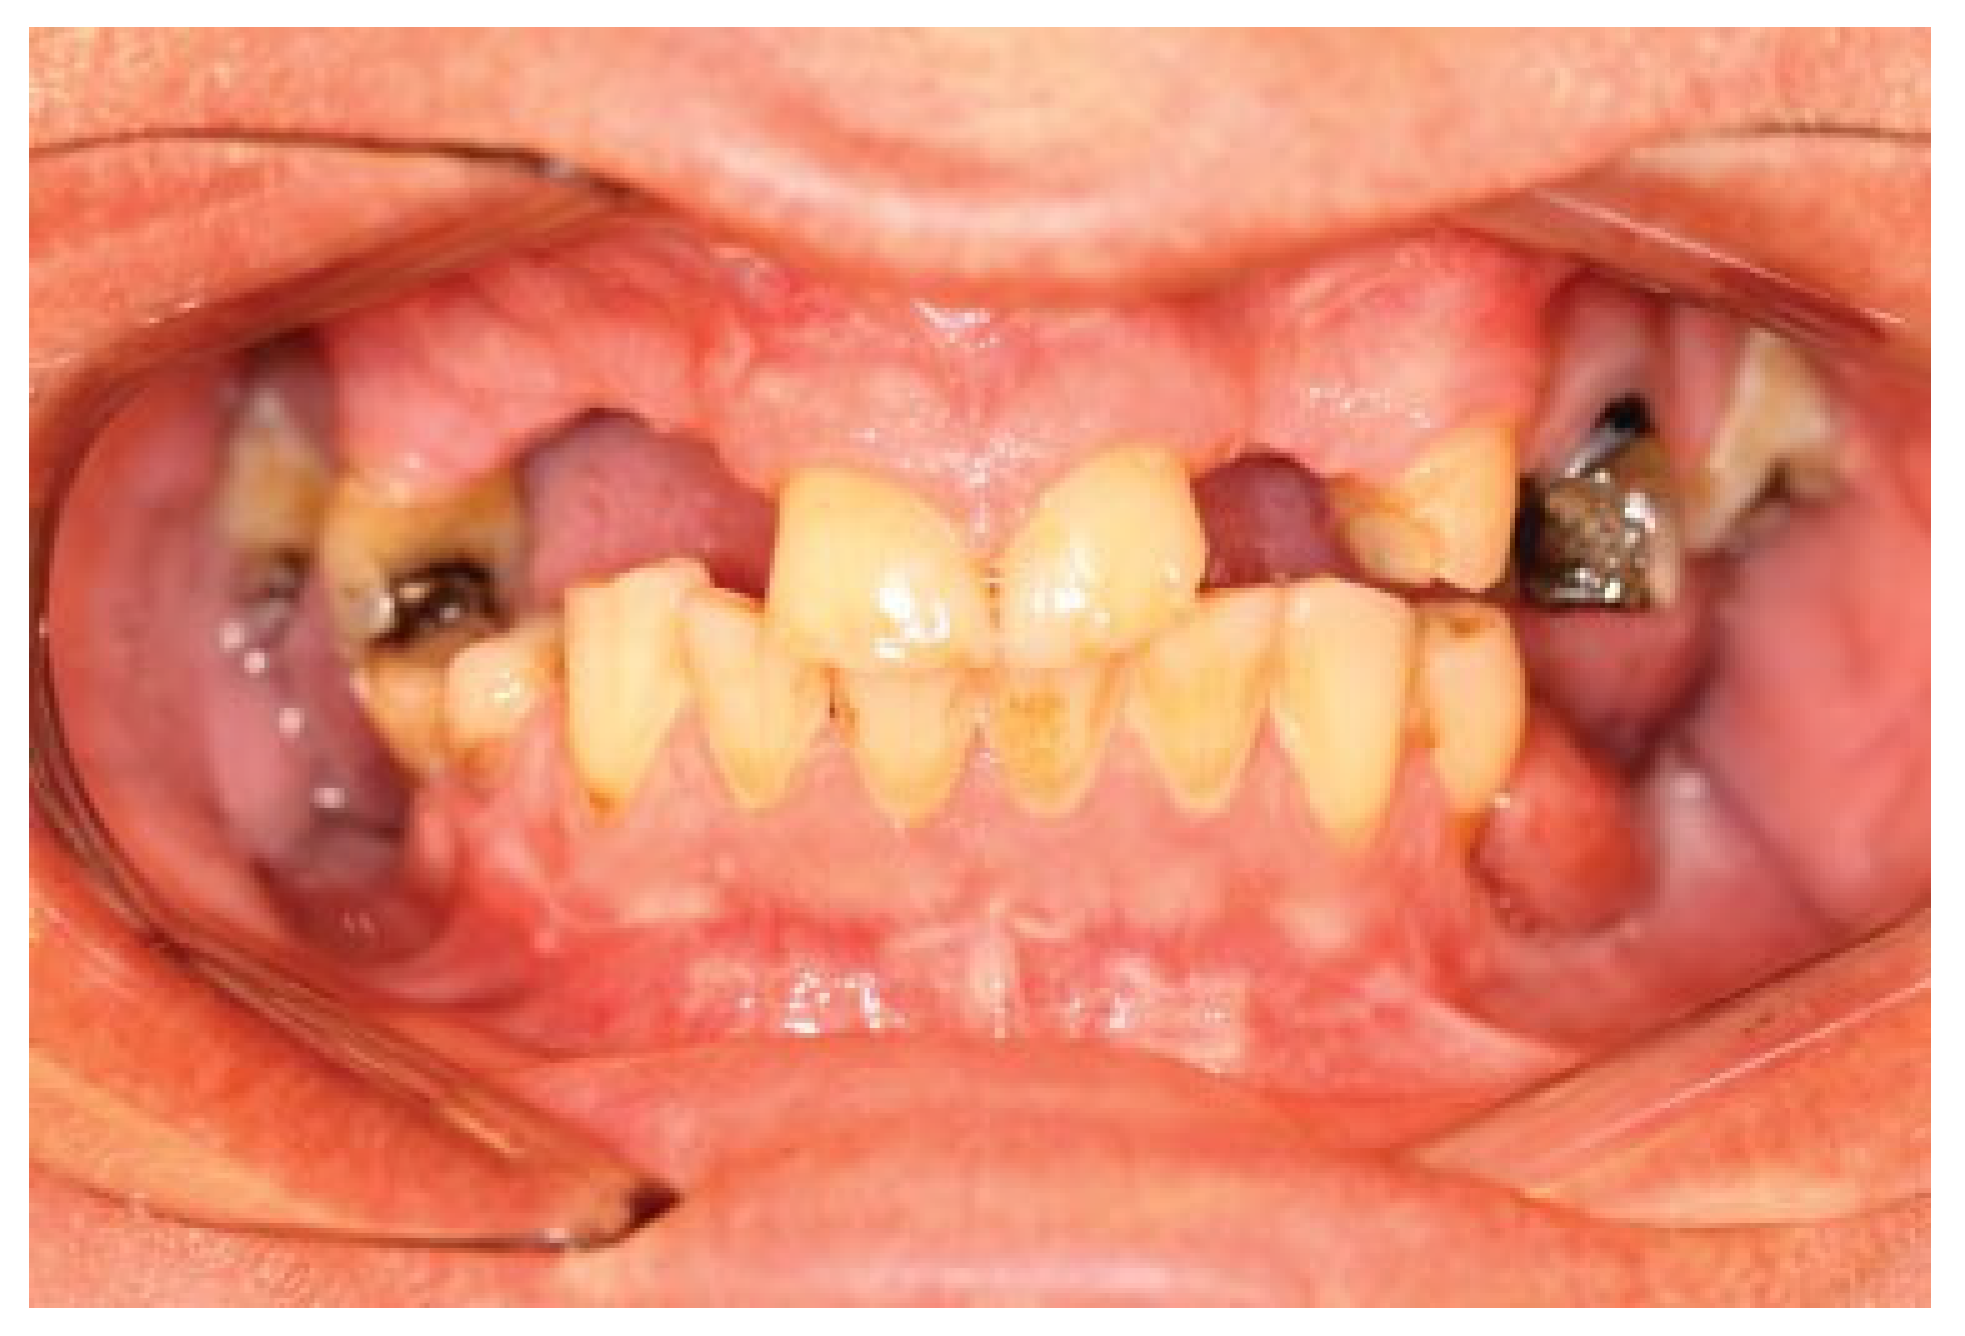

Figure 13.

Occlusion at 6 months follow-up.